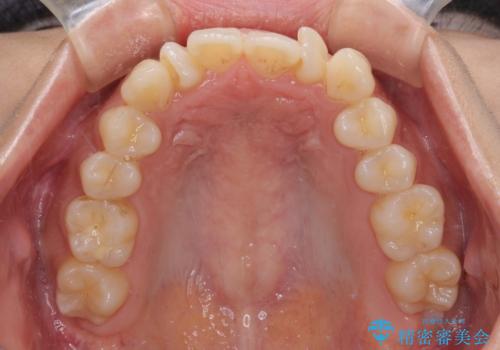

- 上下前歯のねじれを気にして来院された患者様です。

ワイヤー矯正でもマウスピース矯正でも対応可能でしたが、マウスピース矯正の自己管理が面倒であること、上顎前歯の捻転が著しいことから、ワイヤー矯正での治療を希望されました。